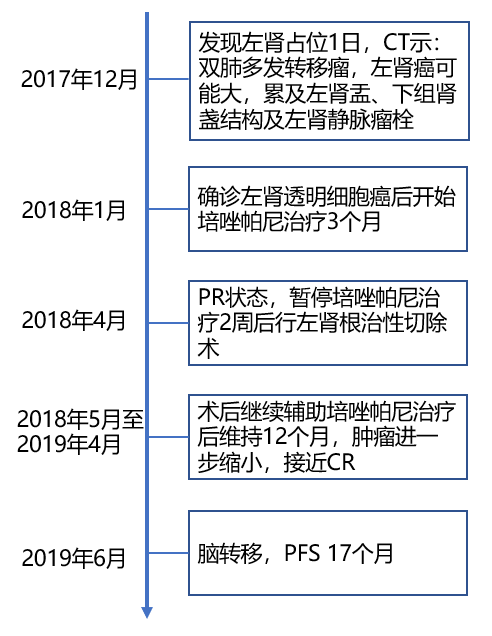

5治疗时间线: